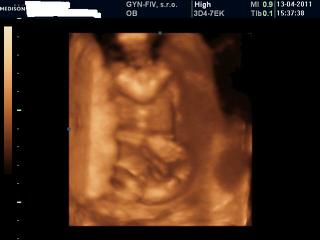

Ja som bola minuly tyzden ked som bola 15+1 na 3D a je to chlapec, vidite to tam ako ja? Mam aj videjka. Fotku Vam tu dam. Takze to vyzera tak ze budeme mat parik🙂)))